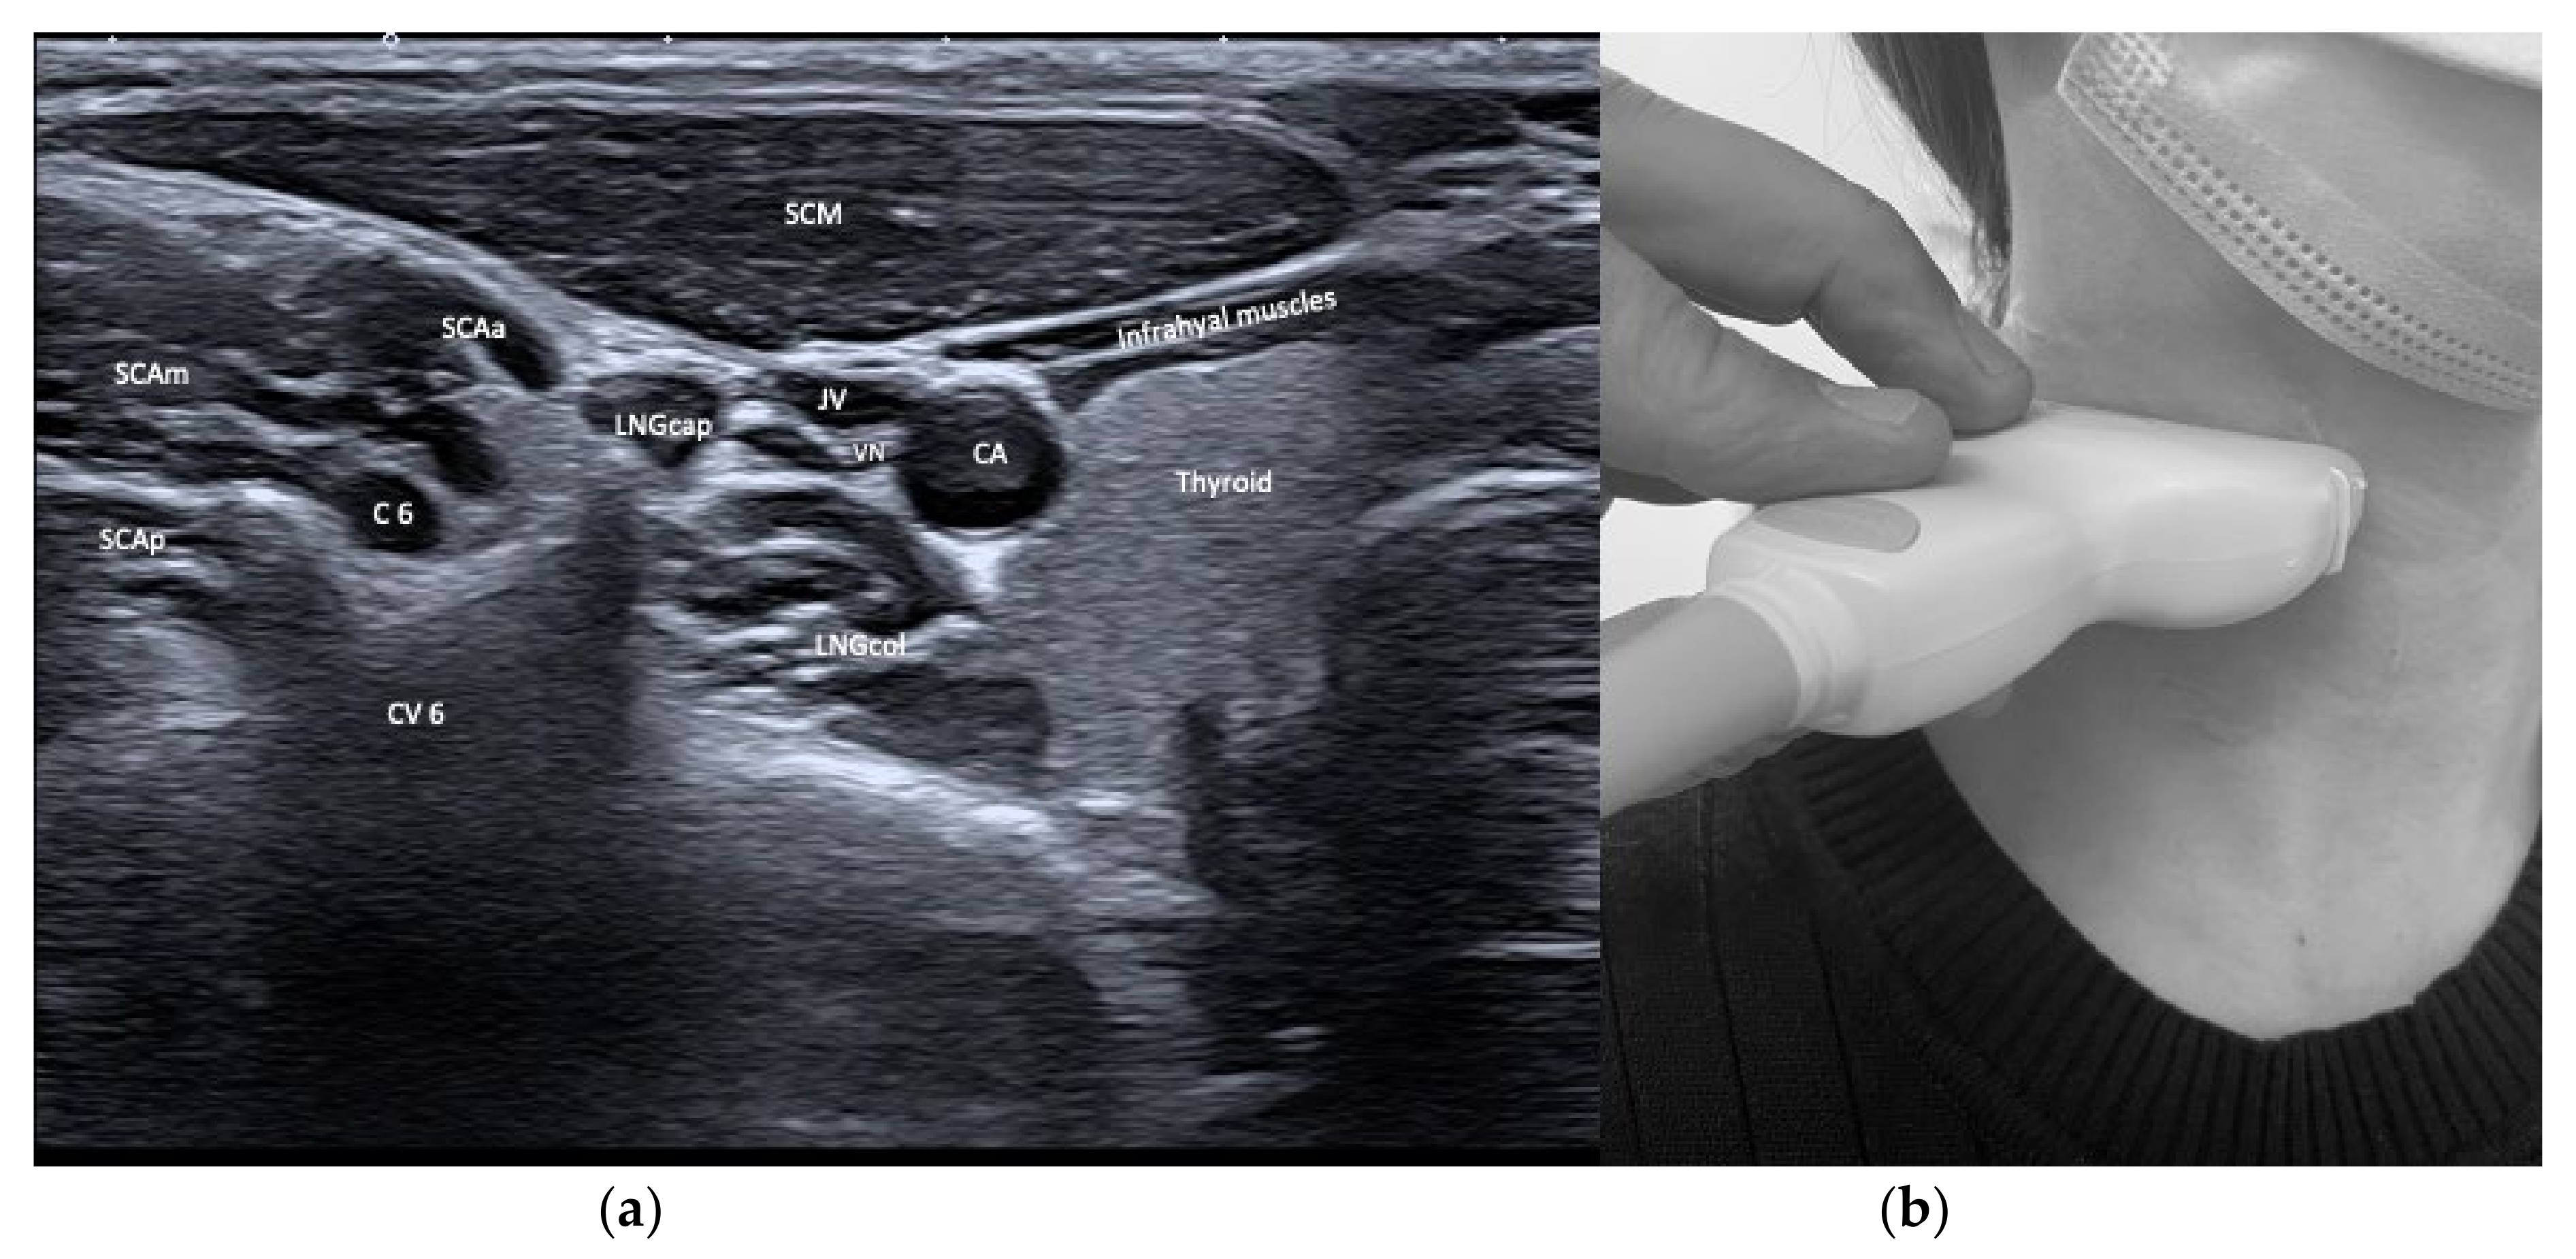

| Longus capitis (LNGcap) | Anteflexion of head and neck | +++ | +++ | Carotid artery, jugular vein, vagus nerve, phrenic nerve | Authors recommend a transoral injection |

| Longus colli (LNGco) | Anteflexion of neck | +++ | +++ | Carotid artery, jugular vein, vagus nerve, phrenic nerve | Authors recommend a transoral injection |

| Scalenus anterior (SCAa) | Anteflexion of neck | +++ | +++ | Thyroid, carotid artery, brachial plexus, phrenic nerve, lung | |

| Sternocleido-mastoid (SCM) | Contraversion of head and neck Ipsitilt of head and neck Anteflexion of head and neck with bilateral activation | + | ++ | Infrahyoid/supra-hyoid muscles, omohyoid, carotid artery, jugular vein | Dysphagia (particularly if injected bilaterally) |